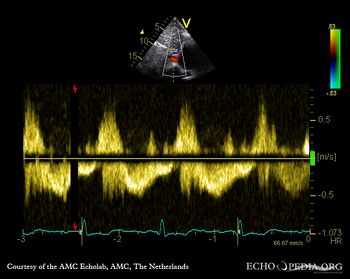

Pulsed-wave signal of hepatic venous flow: systolic flow reversal Continuous-wave signal of transtricuspid flow